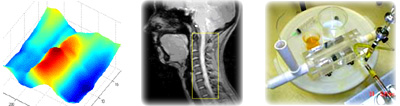

The NIML research program focuses on characterization and modeling of CNS structure/function/biomechanics and linking these findings to the underlying pathophysiology of neurological disorders and potential therapeutics. Researchers agree that biomechanics plays an important role in the pathogenesis and possible treatment options for CNS diseases. Thus, engineering characterization and modeling is a critical step needed to improve clinical care for patients.

CNS research requires multidisciplinary collaboration to make clinical impact. NIML's multidisciplinary research has explored the interface of engineering and life sciences that includes funding for projects with components in cognitive neuropsychology, genetics, advanced MR imaging, metabolomics, molecular biology, machine learning, and intrathecal gene and drug delivery. A summary of ongoing research projects within the NIML are listed below.

• Hydrodynamic Simulator for Brain Therapeutic Development

• NeuroForce Physiologic CSF flow pump

• NeuroFlux Magnetic particle drug delivery to the CNS

• NeuroChi In vitro CSF system models

• MR Measurement and Computational Simulation of Intrathecal Drug Dispersion in Non-human Primates